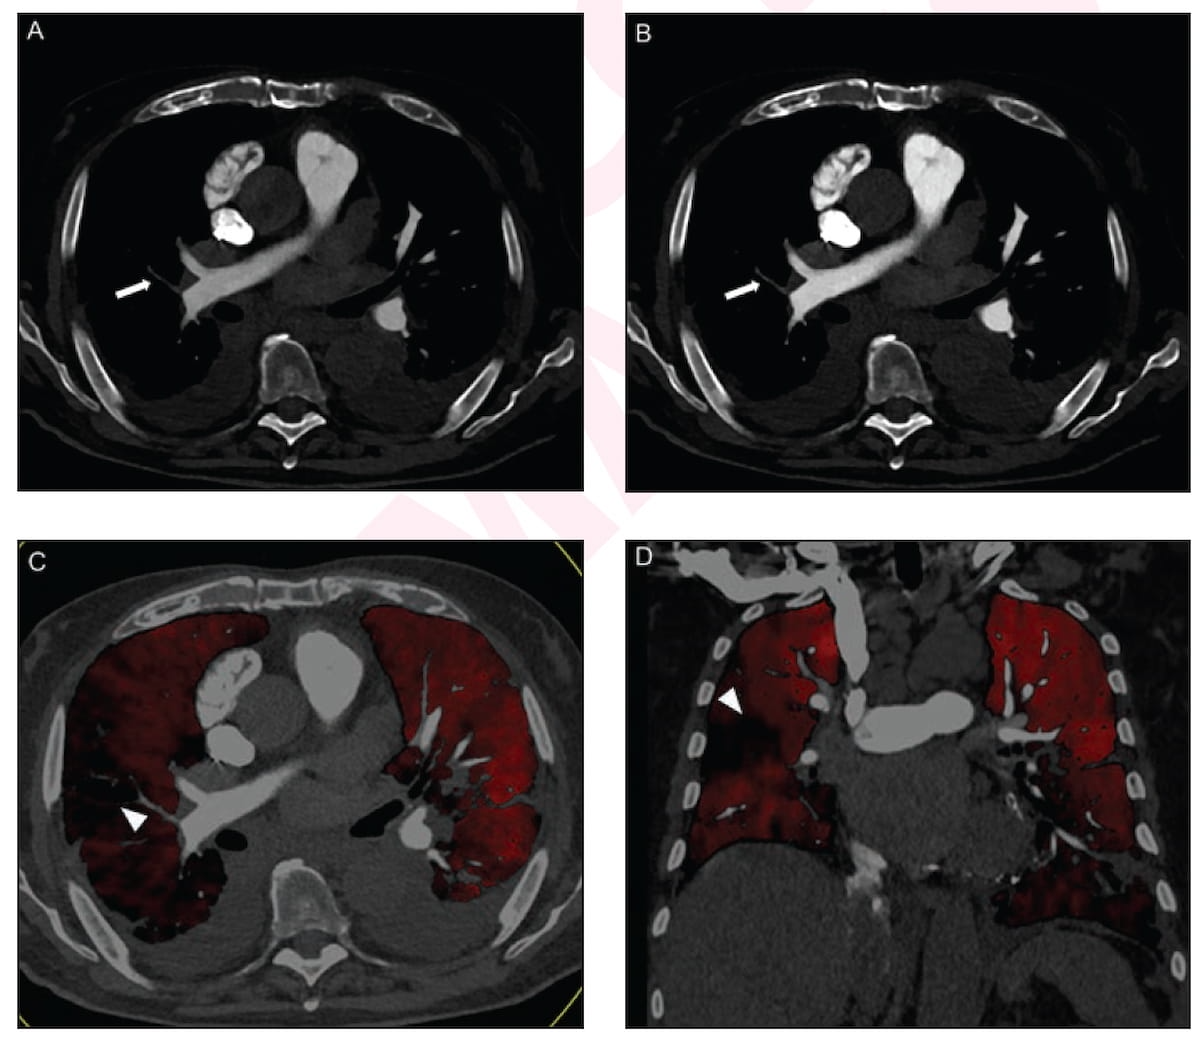

The presence of high-grade hypoattenuation thickening on follow-up computed tomography (CT) after left atrial appendage occlusion (LAAO) procedures for patients with atrial fibrillation was associated with a 4.6-fold risk for stroke, according to newly published research.